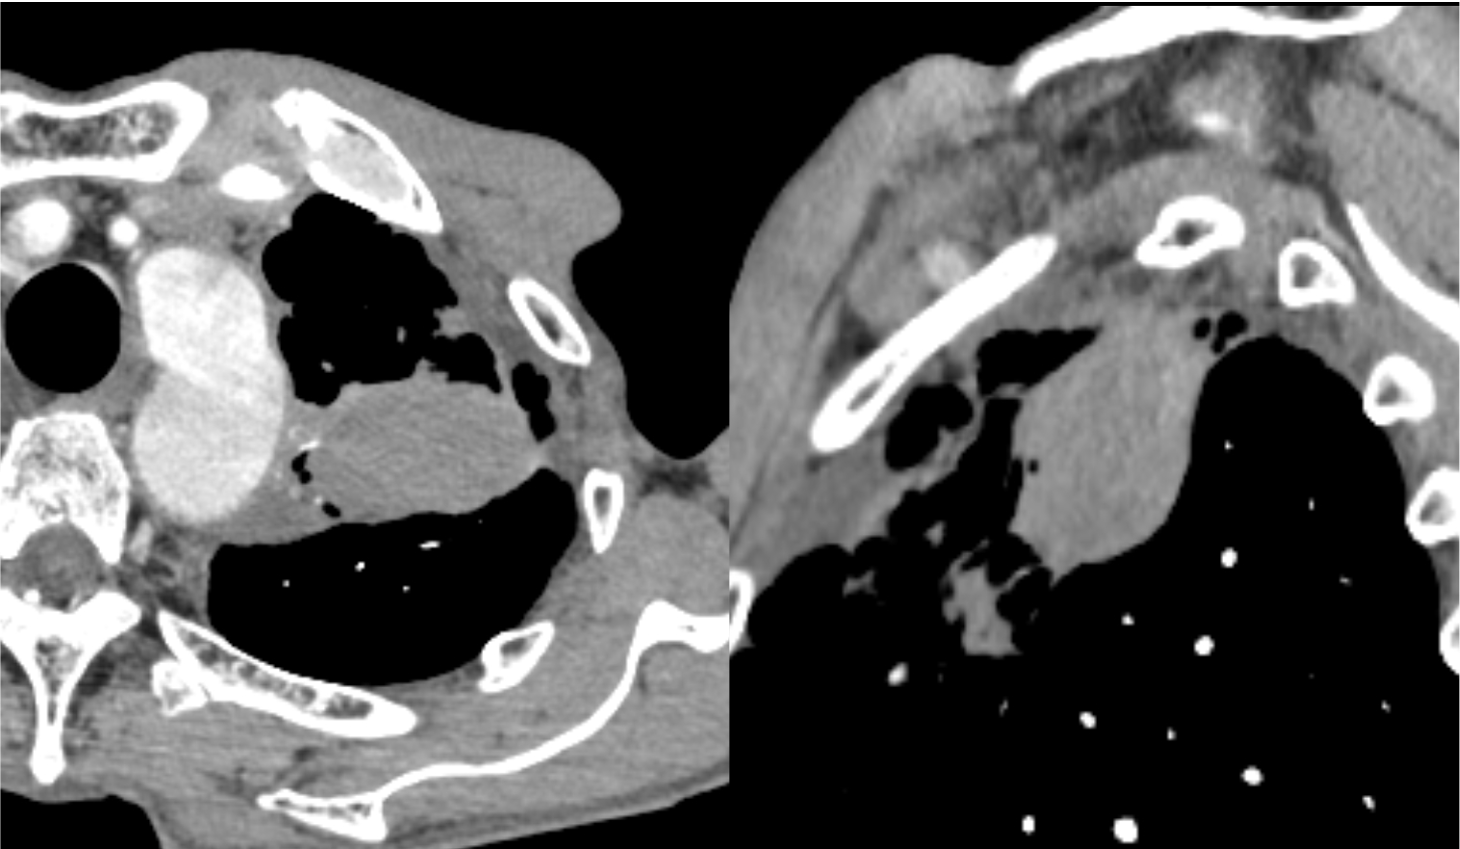

図1.単純CT縦隔条件

左肺上葉に腫瘤を認める。

図2.造影CT早期相

早期相では腫瘤の造影効果は不明瞭である。